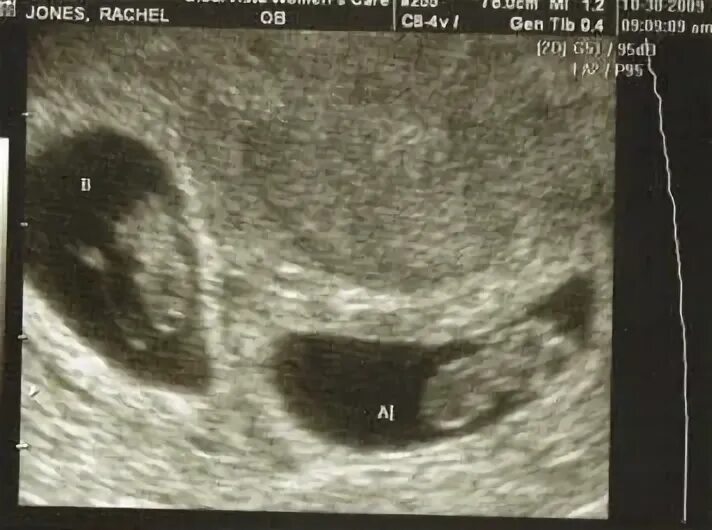

На каком сроке можно увидеть двойню